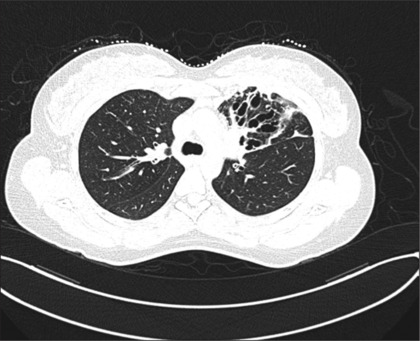

过敏性支气管肺曲霉病(ABPA)是一种由烟曲霉定殖气道引起的超敏反应,主要影响免疫能力强的个体,特别是哮喘患者。ABPA常被误诊为严重哮喘或非缓解性肺炎,导致适当治疗的延误。早期识别ABPA对于预防疾病进展和不必要的抗生素使用至关重要。我们报告一例28岁的女性患者,她有长期控制不佳的哮喘病史,她表现为发烧,咳嗽,放射检查结果最初提示非溶解性肺炎。尽管接受了多个疗程的抗生素治疗,她的症状仍然存在。进一步的调查,包括血清总IgE水平升高、曲霉菌特异性IgE、嗜酸性粒细胞增多和阴性分枝杆菌培养,证实了ABPA的诊断。患者成功接受全身皮质类固醇(强的松)和伊曲康唑治疗,2个月后临床和放射学均有显著改善。她的IgE水平明显下降,支持超敏反应的解决。本病例强调了在哮喘反复发作和不明原因肺部症状患者中识别ABPA的重要性。鉴于有可能被误诊为肺炎,临床医生应保持对ABPA的高度怀疑,特别是在抗生素治疗未能改善的非解决性肺炎的情况下。

Allergic bronchopulmonary aspergillosis (ABPA) is a hypersensitivity reaction triggered by Aspergillus fumigatus colonization of the airways that primarily affects immunocompetent individuals, particularly those with asthma. ABPA can often be misdiagnosed as severe asthma or non-resolving pneumonia, leading to delays in appropriate management. Early recognition of ABPA is crucial to prevent disease progression and unnecessary antibiotic use. We report a case of a 28-year-old female with a long-standing history of poorly controlled asthma who presented with fever, productive cough, and radiographic findings initially suggestive of non-resolving pneumonia. Despite receiving multiple courses of antibiotics, her symptoms persisted. Further investigations, including elevated total serum IgE levels, Aspergillus-specific IgE, eosinophilia, and negative mycobacterial cultures, confirmed a diagnosis of ABPA. The patient was successfully treated with systemic corticosteroids (prednisone) and itraconazole, leading to significant clinical and radiological improvement over 2 months. Her IgE levels markedly decreased, supporting resolution of the hypersensitivity reaction. This case underscores the importance of recognizing ABPA in patients with recurrent asthma exacerbations and unexplained pulmonary symptoms. Given the potential for misdiagnosis as pneumonia, clinicians should maintain a high index of suspicion for ABPA, particularly in cases of non-resolving pneumonia where antibiotic therapy fails to achieve improvement.